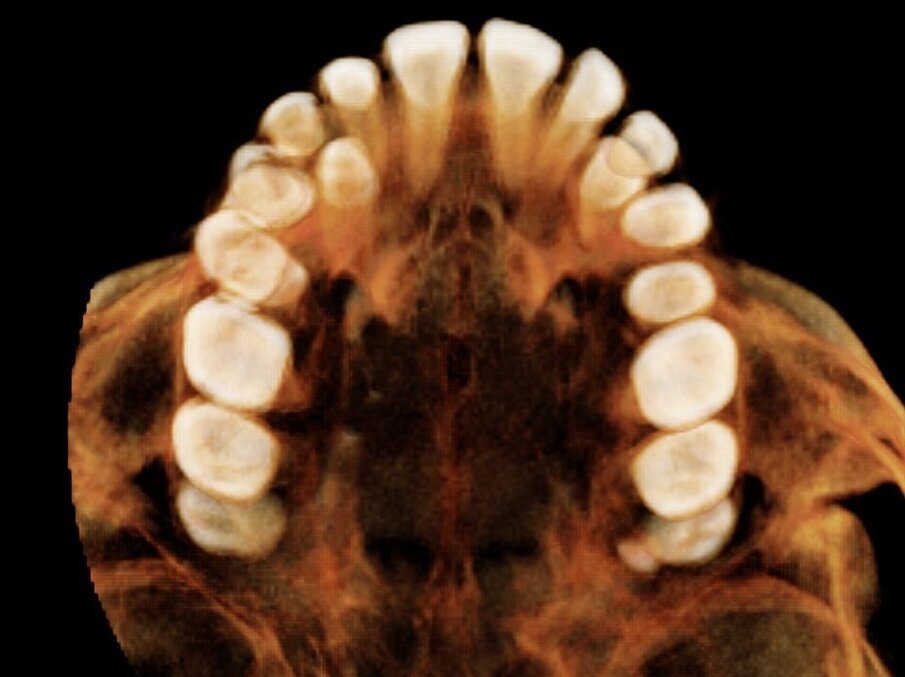

Alessandro, 8 anni, viene sottoposto ad una CBCT (Figg. 21, 22) dopo una valutazione iniziale dove si è riscontrato un percorso di permuta difficile dei canini permanenti (1.3-2.3).

Tramite scansione digitale delle arcate vengono ottenuti dei modelli virtuali, i file .STL vengono inviati al laboratorio ortodontico per la realizzazione di un espansore lento del palato Leaf Expander® (Leone, Sesto Fiorentino (FI), Italia).

Il dispositivo customizzato e prodotto tramite laser sinterizzazione (Fig. 23), viene cementato su “E” e riattivato periodicamente. Dopo la fase di espansione e stabilizzazione (Fig. 24), vengono ottenuti dei nuovi modelli virtuali per la progettazione (Fig. 25) e produzione (Fig. 26) tramite fresatura di una barra di Nance in Trilor® (Bioloren, Seregno, Italia). Alessandro, una volta cementata la barra di Nance (Fig. 27), viene sottoposto ad estrazione anticipata dei canini (5.3-6.3) e dei primi molari decidui (5.4-6.4).

Si ottiene così una normalizzazione della permuta (Figg. 28, 29), che consentirà una seconda fase terapeutica più efficiente.

Fig. 21_CBCT mascellare superiore.

Fig. 22_Dettaglio del percorso di eruzione dei canini.